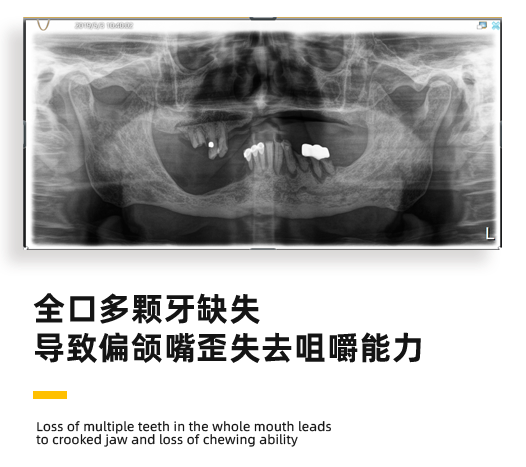

来看诊的时候,恽爷爷全口多颗牙缺失,已经失去了咀嚼的能力。而且因为牙骨缺失,在外观上爷爷的脸已经出现了严重的歪斜。